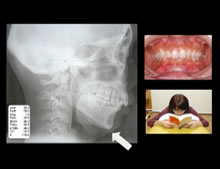

CASE2.前歯が飛び出しているのが気になる

右側の歯並びに大きな変形

横を向いた姿勢でテレビを見る、本を読む

噛みたい位置と実際に噛んでいる位置がずれている。

このような噛み合わせが原因となって顎関節症がひきおこされることも少なくありません。